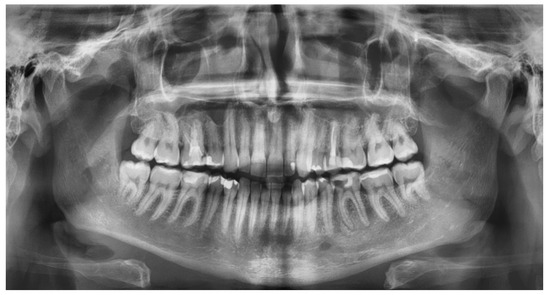

2.2. Radiological Study Protocol

- Maćkowiak, P.; Kaczmarek, E.; Kulczyk, T. Cortical width measurement based on panoramic radiographs using computer-aided system. In Bio-Informatic Systems, Processing and Applications; Abginya, J., Custovic, E., Whittingen, J., Eds.; River Publishers: Aalborg, Denmark, 2013; Volume 2.1, pp. 169–190. [Google Scholar]